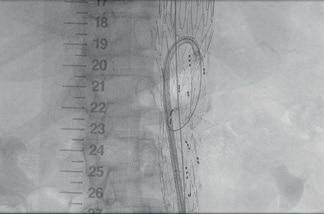

One-year TAMBE data highlight low mortality, importance of renal branch assessment

The four-branch Gore Excluder thoracoabdominal branch endoprosthesis (TAMBE) device demonstrated low mortality at one year with renal artery occlusion being the predominant device-related event associated with small renal arteries and pararenal aneurysms. So concluded Mark A Farber (University of North Carolina at Chapel Hill, Chapel Hill, USA) presenting the latest TAMBE data at the 2025 Vascular Annual Meeting (VAM; 4–7 June, New Orleans, USA).

DRAWING A TAKE-HOME message from the new findings— which were simultaneously published online in the Journal of Vascular Surgery (JVS)—Farber advised: “During follow-up, attention should be focused on renal branch assessment to identify patients at risk for occlusion.”

Farber was presenting one-year results from the pivotal trial of the Gore TAMBE to treat extent IV thoracoabdominal aortic aneurysms (TAAAs) and pararenal aortic aneurysms (PRAAs). Farber detailed that this prospective, non-randomised, multicentre study included 102 patients, 59 of whom had an extent IV TAAA and 43, a PRAA, adding that the mean maximum aneurysm diameter was 59.4mm.

The presenter shared that, at one year, eight patients were lost to follow-up and six patients died, specifying that one death was device-related, one was procedure-related, and four

were due to unrelated causes. He stated that, in total, 88 patients completed a follow-up visit at one year.

Moving on to key results, Farber revealed that freedom from all-cause mortality at one year was 94.1% and that target vessel occlusions occurred in 14.7% of patients. This figure included one celiac artery, one superior mesenteric artery (SMA), eight right renal and six left renal artery occlusions.

Farber continued that reintervention was attempted in six of the renal arteries and involved additional target vessel stenting in three patients, thrombolysis and embolectomy in two, and angioplasty in one. “Although branch vessel occlusion events were more common in pararenal aneurysms compared to extent IV TAAAs, this was not significant,” he said.

Looking at renal patency, Farber reported that

Greenberg Lecture encourages “move beyond” binary aortic

renal artery patency was influenced by renal artery diameter, with renal arteries of less than 5mm in diameter being three times more likely to occlude. He also noted that acute kidney injury requiring dialysis occurred in 1.96% of patients and that renal deterioration— defined as a greater than 25% decrease in glomerular filtration rate (GFR) over two consecutive visits—was 18.9% through one year. Additionally, Farber revealed that renal artery primary patency at one year was 91.8% and “nearly identical between the right and left renal arteries.” Primary patency with respect to renal arteries greater than 5mm in diameter, he continued, was 95.1%, while for those less than 5mm it was 82.5%.

Farber shared that 94.2% of target vessels were free from target vessel instability events through one year. At the individual vessel level, he noted that Kaplan-Meier estimates for freedom from target vessel instability were 99%, 97.1%, 90.8% and 89.8% for the celiac, SMA, right renal and left renal arteries, respectively.

Furthermore, Farber outlined device effectiveness data at one year, which included no major endoleaks, aortic enlargement in 5.4% of patients, and loss of device integrity in 16.3%, which he specified included wire fractures in 3.6% and compression in 12.2%. Farber reiterated that renal deterioration was seen in 18.9%, and that reintervention occurred in 15.6%.

“With respect to the reinterventions,” Farber outlined, “approximately one-quarter were major and included thrombectomy or thrombolysis in five, [and] one exploratory laparotomy for aortic bifurcation rupture to control

bleeding.”

Minor reinterventions, the presenter continued, included treatment of target vessel stenosis in eight patients, target vessel occlusion in two and branchrelated endoleak treatment in three.

Revealing overall device performance data, Farber shared that combined device effectiveness was achieved in 60.5% and 78.7% of the pararenal and type 4 TAAAs, respectively. “This difference was mainly driven by a higher incidence of target lesion growth and branch vessel occlusion in pararenal aortic aneurysms,” the presenter commented.

In the discussion following Farber’s presentation, Wes Moore (David Geffen School of Medicine at UCLA, Los Angeles, USA) asked how the new data might weigh up to those for physician-modified endovascular grafts (PMEGs).

“It’s hard to compare those results because we’re talking about a fourbranch off-the-shelf device, and the majority of the PMEGs are probably fenestrations or laser fenestrations depending upon where you are, and so it’s hard to compare those,” Farber responded.

The presenter continued: “The important part about the manuscript is that we know that there are renal events that occur and that the goal of this manuscript is to talk about how you can help select your patients better. We have some renal events and 95% patency if you’re greater than 5mm at a year. If you have a patient who has small renal arteries, you need to think about how this might impact them since renal function is linked to survival.”